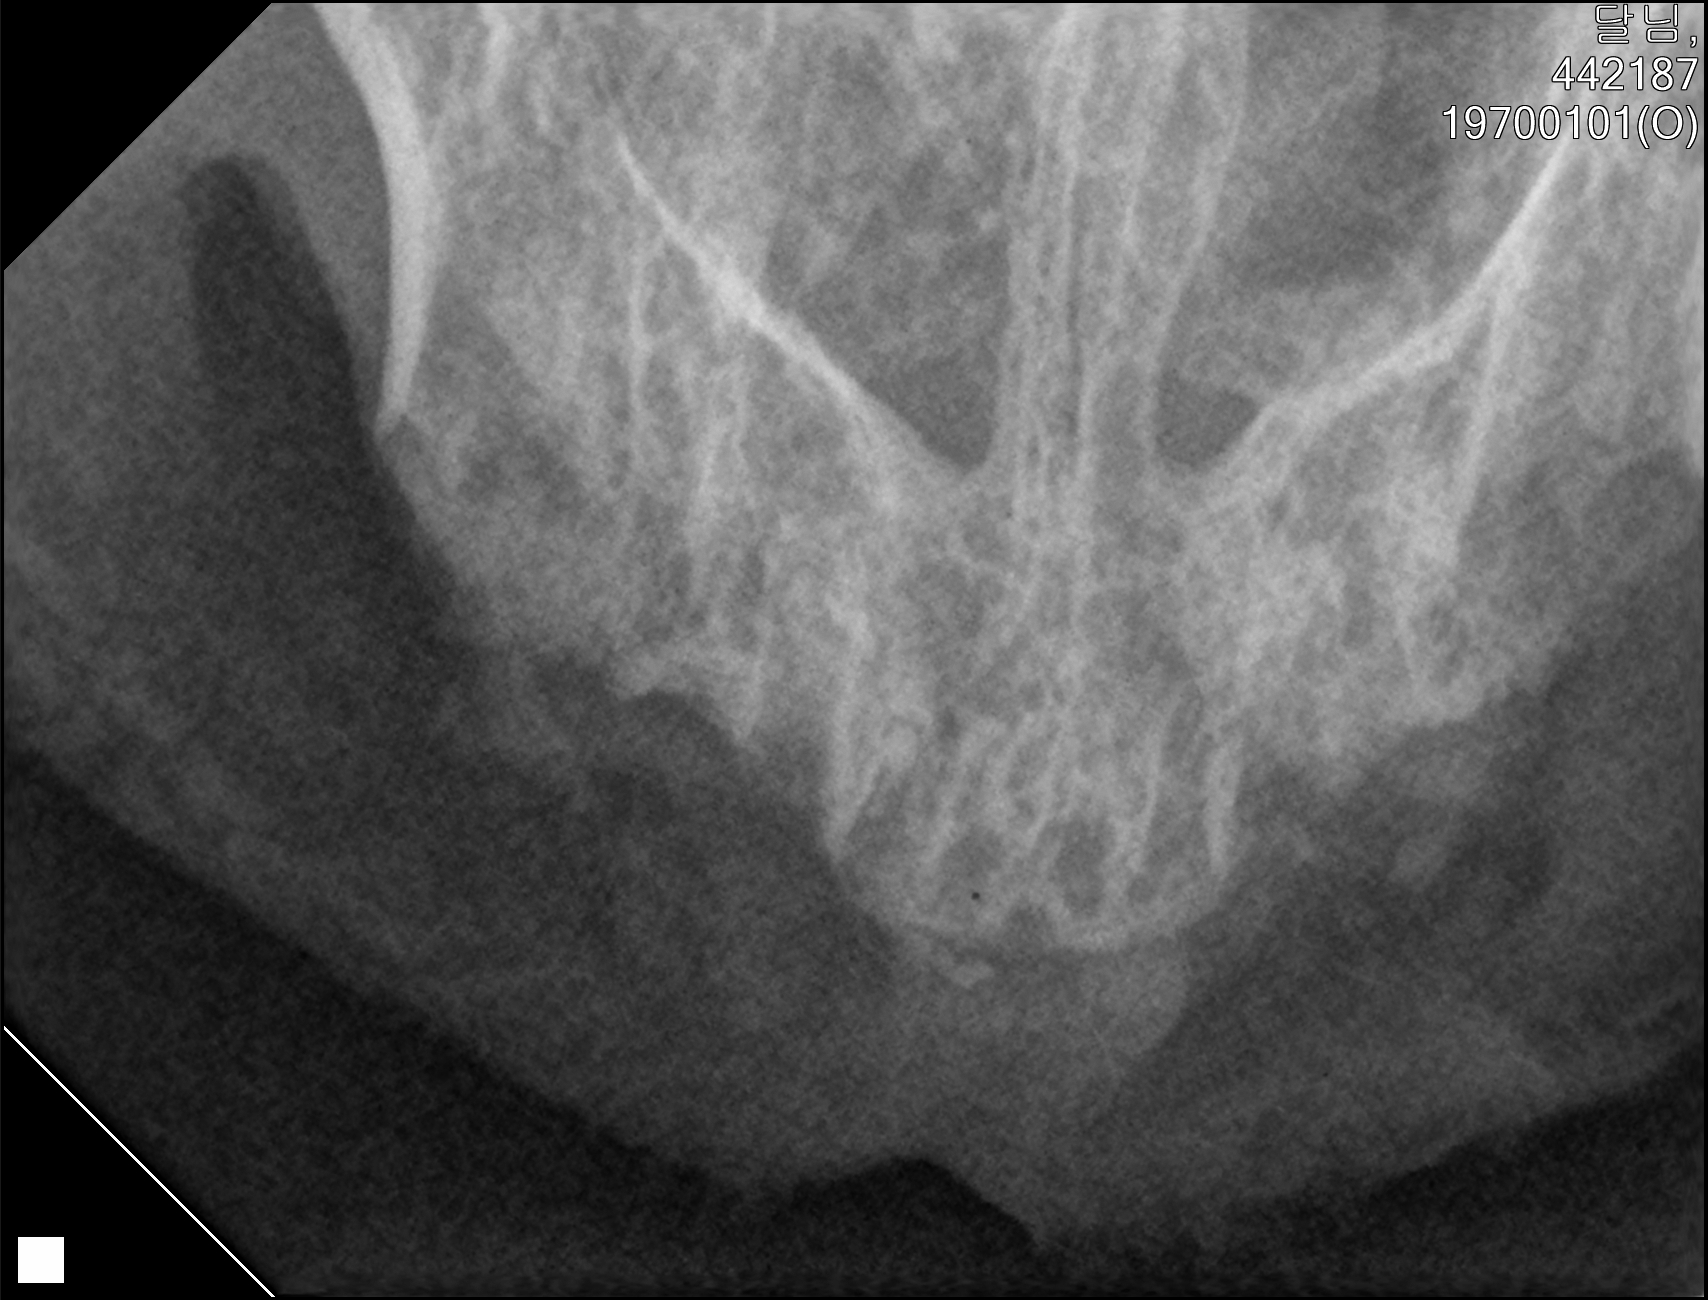

| 치료과정 | 달님이를 병원에 데려갔을때 거의 한달 가까이 먹질 못했기 때문에 몸무게는 2키로 초반대로 나갔고 마취하고 검사할수있는 상태가 아니였기 때문에 피검사를 통해서 간단히 검사후 입원하기 시작했습니다 탈수증세가 너무 심했고 수액을 맞으면서 자발식을 찾으려 했지만 달님이는 전혀 먹질 않았고 입원기간도 길어지게 되었습니다 그 와중에 청천벽력같은 소리를 듣게되었습니다 신장수치가 좋지않아 신부전이라는 결과였습니다 손도안타는 이아이를 제가 과연 케어할수있을까 너무 너무 걱정이였고 눈물이 앞을 가렸습니다 하지만 우선 체력을 회복한후 걱정은 나중에 하기로하고 달님이 치료에 집중하기 시작했습니다 병원에서도 선생님들이 달님이를 강제 급여도 해주고 수액도 계속 맞고 보니 꽉 막혀있던 코에서 콧물도 나고 소변도 보기 시작했습니다 그리고 다시 검사를 하고나니 다행히 신부전은 아니고 지방간이라고 하였습니다 아마도 오래전부터 먹는양이 줄어들었고 최근에 들어 아예 먹질못해서 간이 망가졌고 황달증세가 생겼다고합니다 어떤 이유에서인지모르겠지만 달님이는 원래 호흡기도 안좋았고 항상 콧물과 재채기를 달고산 아이라 호흡기도 안좋았고 이빨상태도 안좋아 밥을 못먹기 시작했던거같습니다 우선 체력회복이 중요하기때문에 집에서 케어한후 간 회복후 추후에 발치를 하기로 하였습니다 집에 온후 달님이는 바로 사료를 먹기시작했습니다 아마도 병원이 싫어서 밥을 안먹었던 모양입니다 매일 처방식과 약을 먹이면서 살을 찌우기 위해 이것저것 달님이가 좋아하는 캔과 츄르를 바치기 시작했고 다행히 달님이는 매일 맛있는 밥을 먹으며 살이 찌기시작했습니다 한달되는 날 발치와 검사를 위해 병원에 가서 검사를 하였는데 달님이는 3.86키로로 몸무게도 상당히 늘었으며 검사결과 모든 수치가 좋아졌습니다 그리고 마취후 이빨상태를 보니 치주염이 심각했고 이빨은 어금니부터 송곳니까지 다 내려앉은 상태였습니다 입안은 구내염이 시작되었고 원장님은 송곳니도 지금도 안좋지만 나중에 되면 더 아퍼질꺼라며 전발치를 해야한다 하였고 저는 달님이과 전발치를하고 길에서 잘 살수있을까 너무 걱정이였지만 나중에 아파서 또 구조후 마취하는것보다 낫다고 생각했고 밥자리도 잘 되어있어 전발치하고도 잘사는길냥이들 많다고 들어서 전발치를하게되었습니다 달님이는 수술을 잘 마쳤고 퇴원후 달님이는 집에서 10일정도는 약먹고 회복해야하기때문에 집에서 좀더 케어한후 방사할 예정입니다 |